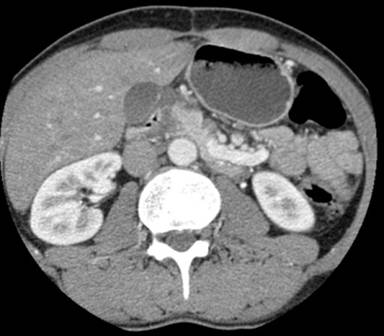

All five patients underwent an initial abdominal CT scan. Three patients had subsequent imaging with MRCP or EUS and one patient had both. In all cases duodenal wall thickening was present. Four patients showed changes at the pancreatic head, either an ill-defined mass or a swollen head of pancreas (Figure 1). Bile duct dilation was noted in four of the five cases. MRI and EUS observations correlated well with CT findings providing additional information in all cases: pancreatic duct dilation, duodenal wall thickening and bile duct dilation.

Figure 1. Contrast enhanced CT scan demonstrating an ill-defined hypoechoic mass in the head of the pancreas. |